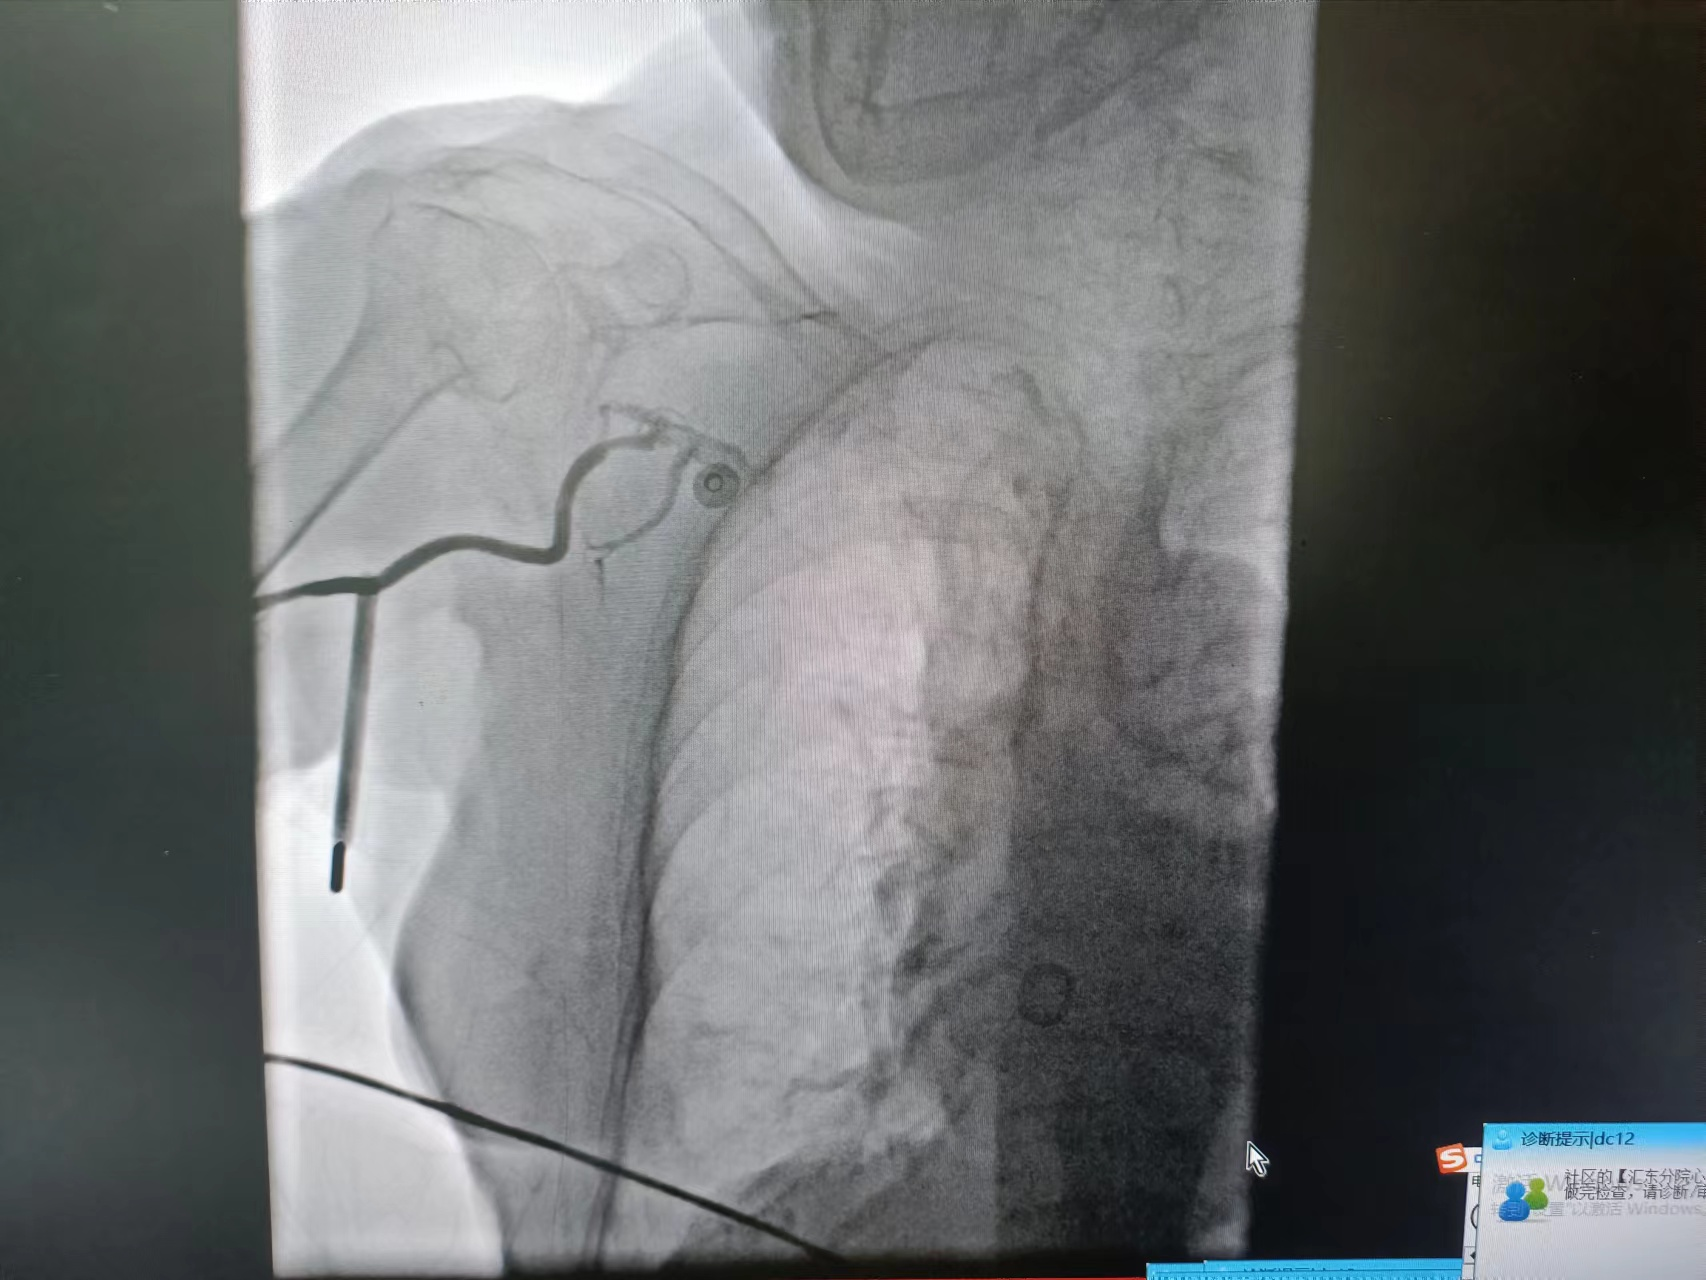

![]() ![]() ![]() 术前冠脉造影

![]() 术后冠脉造影

植入支架发生慢血流

血流恢复